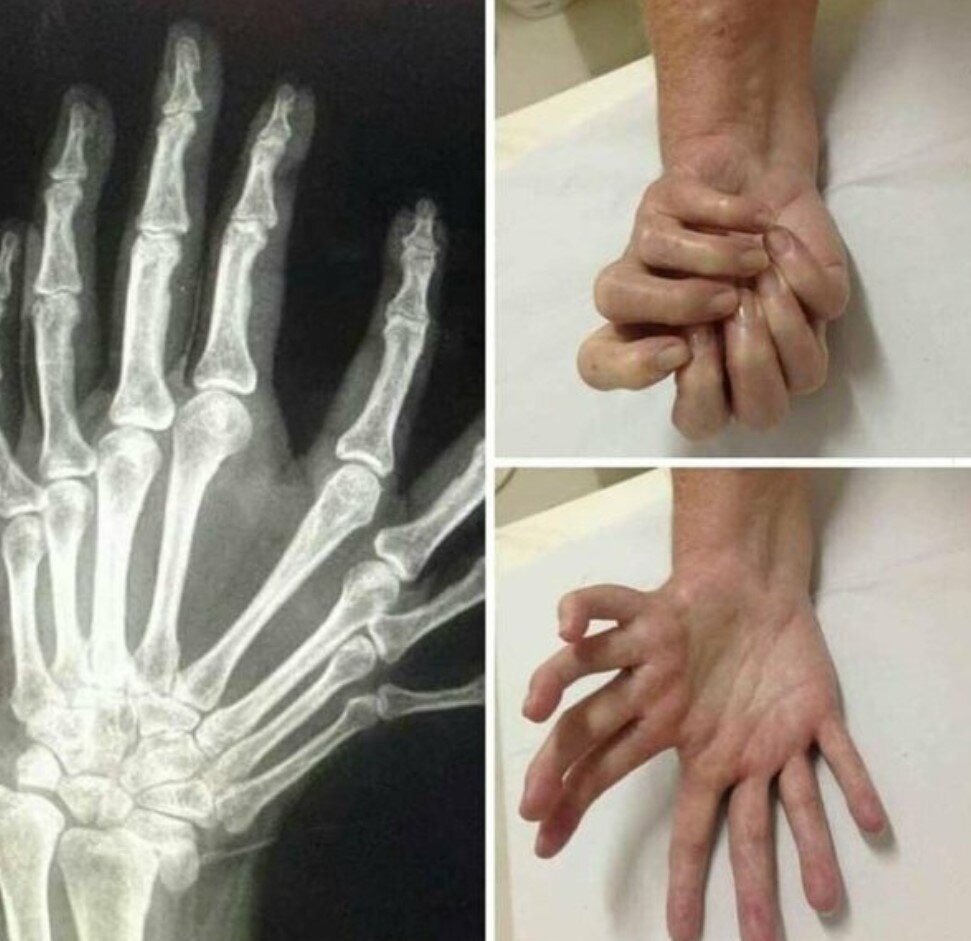

Синдром зеркальной руки - чрезвычайно редкий синдром, который был диагностирован всего 100 раз во всем мире. Его также называют локтевой димелией. Болезнь не является наследственной и может быть вызвана генетической мутацией. Кисти часто соединяются на ладони и, как правило, симметричны. Рука пострадавшего выглядит так, как будто она сложена вдвое. Дополнительные пальцы соединены с дополнительными костями, которые проходят вдоль запястья пользователя и иногда доходят до локтя. Впервые это заболевание было описано в 1587 году, но с момента этого открытия в медицинской литературе было задокументировано только 72 случая, и некоторые случаи, возможно, остались незамеченными в слаборазвитых частях мира. Одна из попыток сделать этих людей "презентабельными" выглядит так. Это маленький Эван через семь недель после операции, и я думаю, что принцип "меньше значит лучше" применим в данной ситуации. Если Вам понравилась статья, делитесь, комментируйте и ставьте лайк, это помогает каналу. Так же ч

Синдром зеркальной руки - чрезвычайно редкий синдром, который был диагностирован всего 100 раз во всем мире.

Его также называют локтевой димелией. Болезнь не является наследственной и может быть вызвана генетической мутацией. Кисти часто соединяются на ладони и, как правило, симметричны.

Рука пострадавшего выглядит так, как будто она сложена вдвое.

Дополнительные пальцы соединены с дополнительными костями, которые проходят вдоль запястья пользователя и иногда доходят до локтя.

Впервые это заболевание было описано в 1587 году, но с момента этого открытия в медицинской литературе было задокументировано только 72 случая, и некоторые случаи, возможно, остались незамеченными в слаборазвитых частях мира.